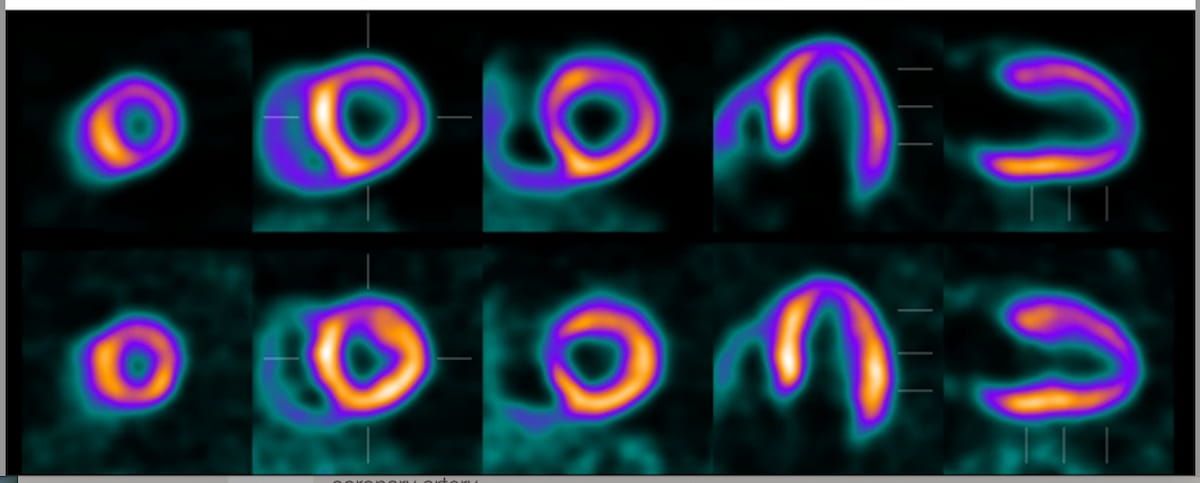

Stay updated with the latest in radiology, including PET, MRI, and AI research, plus essential insights on mammography and cardiac imaging.